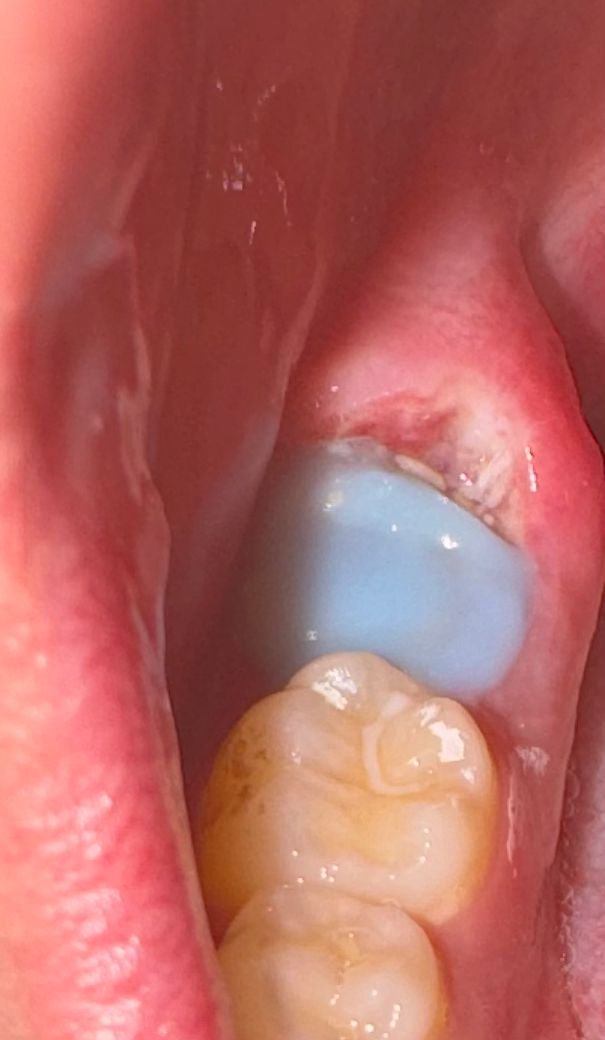

임시 치아 치료가 제대로 된건지 의심이 들어요

제가 충치를 제거하고 지금 잠시 임시 치아를 달아놓은 상태입니다..2주 뒤에 상황을 보고 신경 치료를 진행하거나, 아니면 그냥 이빨을 본떠서 가짜 이빨을 심어줄거라고 하네여

그런데 임시 치아 뒤쪽에 절개한 잇몸이랑 빈 공간이 좀 있는거 같아서 여기에 음식물이 쌓여서 충치가 악화되지 않을까 걱정됩니다…혀끝으로 만져보면 공간이 느껴져요

(혐주의)치과 선생님들 확인좀 부탁드립니다 ㅠ 이 빈 공간 괜찮은건가요?

안녕하세요 치과의사 김철진입니다.  뒤쪽에 공간이 있는거 같은데 시리거나 불편하시면 치과에가셔서 다시 해달라고 하시는게 좋을것같습니다

• 임시치아이기 때문에 틈이 있다고 해서 그다지 문제가 생기지는 않습니다. 2주동안 상태체크를 위해 임시로 한 것이고 정기적인 체크가 있을것이니 음식물도 너무 걱정안하셔도 됩니다.

• 사진으로는 정확한 판단이 힘들어 보이나 보철치료를 하기 위해서 보철을 씌워야 되는 부위를 노출시키기 위해서 잇몸을 다듬었을 가능성이 높습니다. 자세한 확인을 위해서 치과에서 진료를 받아보는 것을 권유드립니다